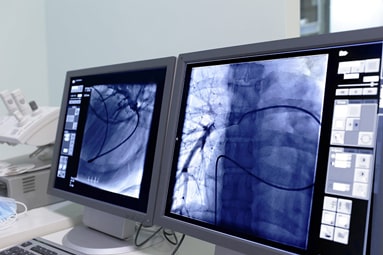

Interventional Cardiology

Experience a spectrum of procedures to repair heart problems.